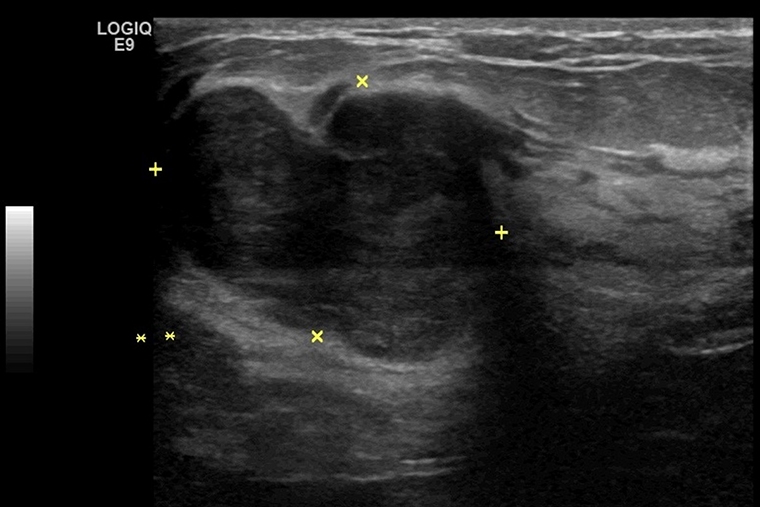

【NOW健康 林郁敏/新北報導】30歲的許小姐日前摸到左側乳房有明顯腫塊,且短期內快速變大,因此至台北慈濟醫院一般外科醫師陳昱天門診。經乳房超音波與粗針切片檢查發現有約3公分大的葉狀瘤及2顆小腫瘤,考量許小姐的病灶接近乳頭且其他小腫瘤,也無法排除是否為葉狀瘤,最終執行內視鏡輔助微創乳房全切除手術合併重建,手術確認為良性,所幸手術順利,腫瘤完全切除,後續追蹤未見復發。

許多病人最關心的問題是「這個腫塊會不會是癌症?」,陳昱天指出,判斷乳房腫瘤是否惡性,必須透過影像檢查與病理切片,層層檢驗,才能作出正確診斷與治療建議。乳房超音波與乳房攝影是腫瘤評估的主要影像工具,各有其適用族群與優勢。乳房超音波特別適用於年輕女性,因其乳腺較緻密,可清楚區分腫塊是液體囊腫還是實質腫瘤,並觀察腫瘤的邊界、形狀與血流分布,協助判斷良惡性。